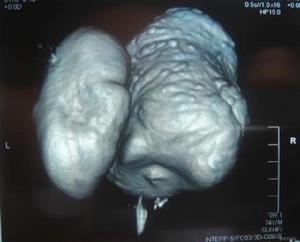

1.鋇餐造影檢查影像表現為:多發生在膈面上方5~6cm處,以食管右側多見,食管一側壁類圓形突出,口部可窄小或寬大,邊緣光滑,大小隨食管的收縮舒張而變化。鋇劑容易貯留而不易排出,故憩室體積較大,其內常因有食物殘渣而密度不均,易發生感染,甚至壞死穿孔。鋇餐造影檢查不僅可以顯示膈上食管憩的具體部位、大小、憩室囊、憩室頸部及其方向、憩室的外形、食管腔的最大擴張度以及局部食管壁缺損的長度,還可明確有無與膈上食管憩室有關的其他疾病,如食管神經肌肉功能紊亂、食管裂孔疝、賁門失弛緩症、食管狹窄或憩室癌,其中膈上食管憩室合併食管裂孔疝的病例最為常見。

2.內鏡檢查可以發現膈上食管憩室有無炎症、潰瘍形成、憩室癌和食管梗阻的程度;病人有上消化道出血,內鏡檢查可以明確出血的來源。體積大的膈上食管憩室可使食管發生移位,因此內鏡檢查有發生憩室穿孔的可能,檢查過程中須特別小心。膈上食管憩室可並發潰瘍、出血或自發性憩室穿孔。有的病例發生憩室出血後出血較為嚴重,須手術切除憩室後方能控制出血。憩室本身可發生返流和誤吸,而誤吸可引起吸入性肺炎和肺膿腫。據文獻報導,膈上食管憩室可發生腫瘤,如發生纖維瘤、平滑肌瘤和鱗癌。體積較大的憩室內食物和分泌物鬱積或滯留、慢性感染以及憩室內容物腐敗等因素可能促進憩室發生癌腫。食管鋇餐造影顯示膈上食管憩室的輪廓不規則或其形態較前縮小,疑有憩室癌腫發生時,應及時行食管鏡檢查。